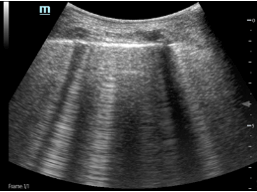

C1.  C2.

Figure C. Image C1 is a real-time scan of a normal lung with POCUS. Figure C2 is a CT scan of a patient who had a collection of some fluid in the chest.